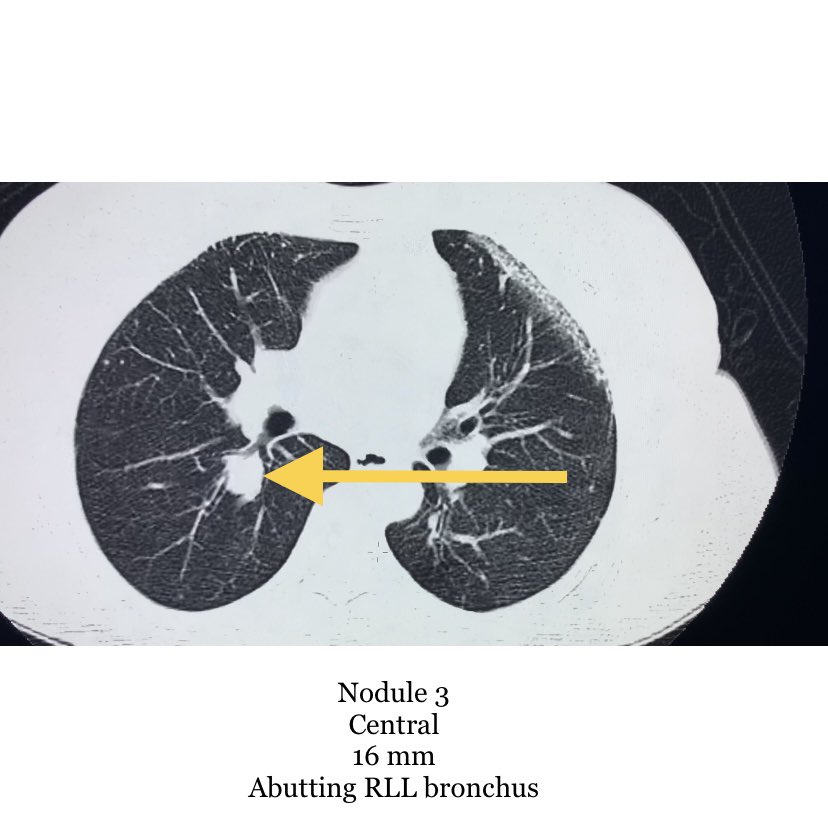

Reference for CT guided lung lesion biopsy. Nodule preference for biopsy and why?

Nodule 1, 2, 3 or 4?

@evascularrounds @bhavinj @SRajesh_IR @No_cut_surgery @keithppereira @lenonjdee @_backtable @Dr_AkshayBaheti @SandeepBaglaMD @iRadRock @TomG_IR @Watts_IR @IrShaileshgupta @vascularIR Agreed, I would go for #4. Large enough to get adequate tissue, peripheral enough to limit risks. While I often like anterior approaches to enable supine positioning, the breast tissue, IMA, and small nodule size make #1 a little more complicated.